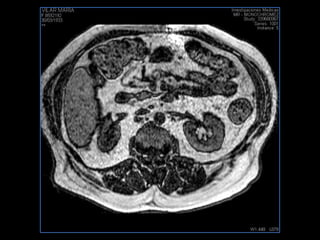

PROTOCOLO abdomen COR T2, AXIAL supresion grasa AX T1 +SAG T2  CON   GADOLINIO :  COR T1+AX T1(DIN) SAT: NO  FASE: RL THK: 6MM  COIL:  GAP: (FACTOR 1.4) 2MM FOV: 40 CM NEX:2 SINCRONIZACION RESPIRATORIA EN 3 O 4 CICLOS ALE

resonancia de abdomen